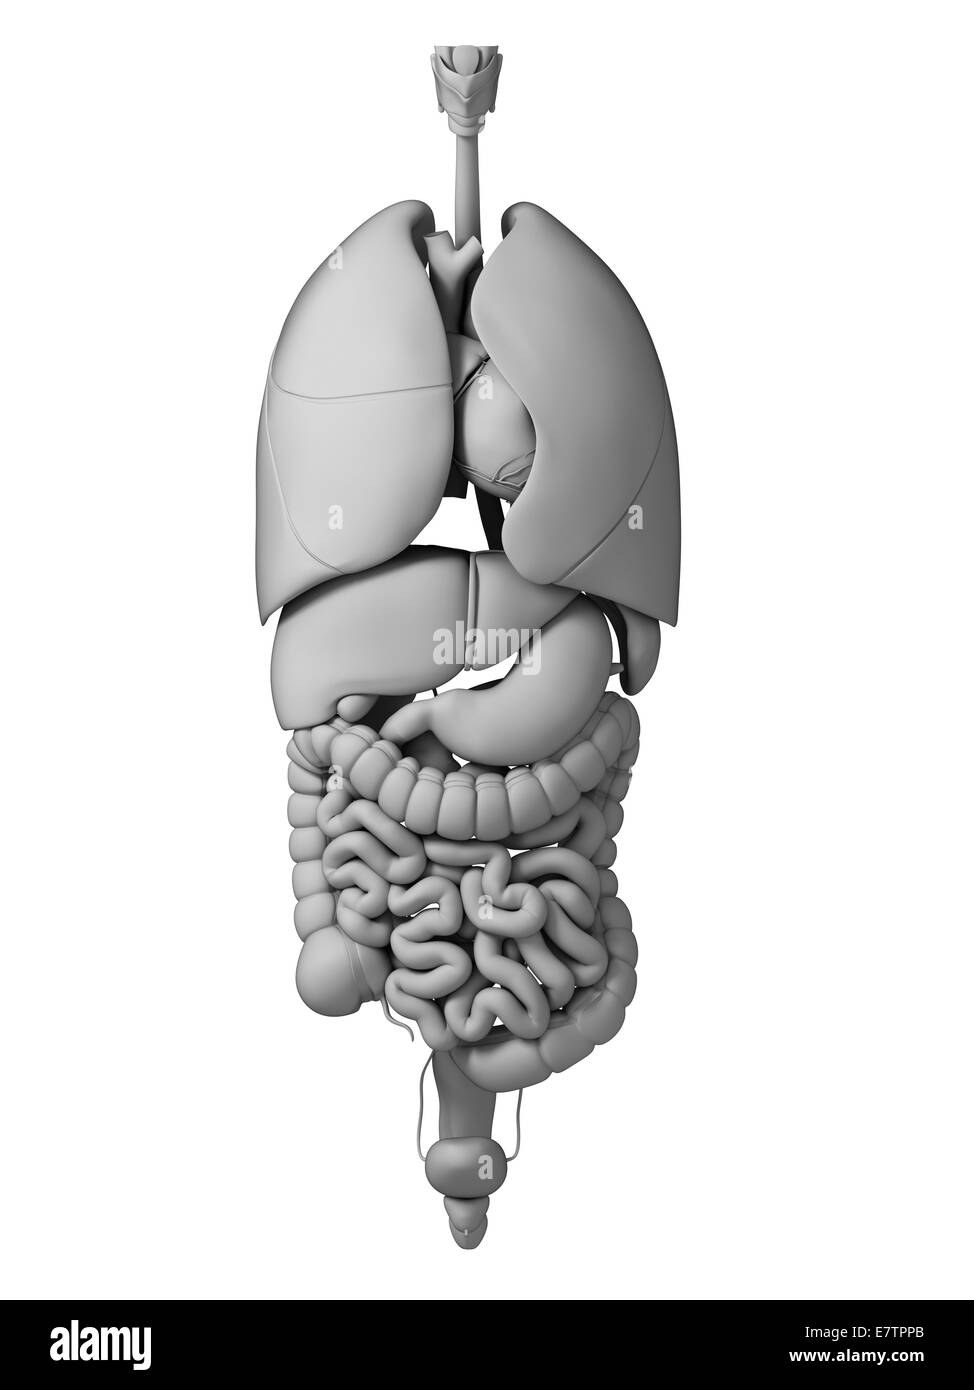

Internal human anatomy and organ systems Stock Photohttps://www.alamy.com/image-license-details/?v=1https://www.alamy.com/internal-human-anatomy-and-organ-systems-image61889397.html

Internal human anatomy and organ systems Stock Photohttps://www.alamy.com/image-license-details/?v=1https://www.alamy.com/internal-human-anatomy-and-organ-systems-image61889397.htmlRFDGK8FH–Internal human anatomy and organ systems

Human internal organs, computer artwork. Stock Photohttps://www.alamy.com/image-license-details/?v=1https://www.alamy.com/stock-photo-human-internal-organs-computer-artwork-73688787.html

Human internal organs, computer artwork. Stock Photohttps://www.alamy.com/image-license-details/?v=1https://www.alamy.com/stock-photo-human-internal-organs-computer-artwork-73688787.htmlRFE7TPPB–Human internal organs, computer artwork.